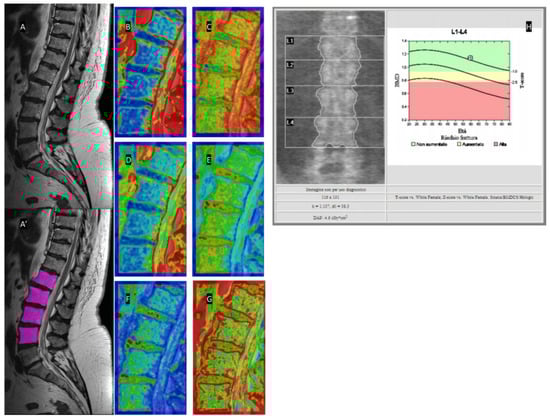

2.4. MRI

2.5. Texture Analysis